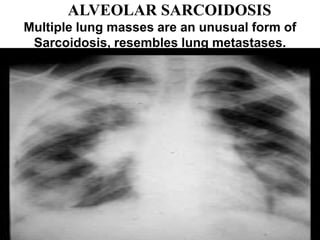

ALVEOLAR SARCOIDOSIS

Multiple lung masses are an unusual form of

Sarcoidosis, resembles lung metastases.